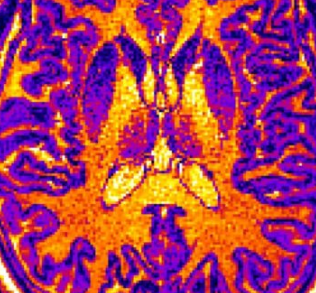

像这样的MRI图像通过机器学习计算机算法进行筛选。该算法基于大脑某些区域的厚度,体积或表面积的细微但统计上重要的差异,学会了识别非患者,诊断为自闭症的患者和诊断为精神分裂症的患者的大脑。该工具可能有助于使将来的心理健康诊断更加客观,而不是仅仅依靠患者及其家人的陈述。图片来源:CC-BY /东京大学小池真辅

大多数现代医学都有物理测试或客观技术来定义使我们感到不适的许多疾病。但是,目前还没有血液,基因检测或公正的程序可以明确诊断精神疾病,当然也没有人可以区分具有相似症状的不同精神疾病。东京大学的专家正在将机器学习与脑成像工具相结合,以重新定义诊断精神疾病的标准。